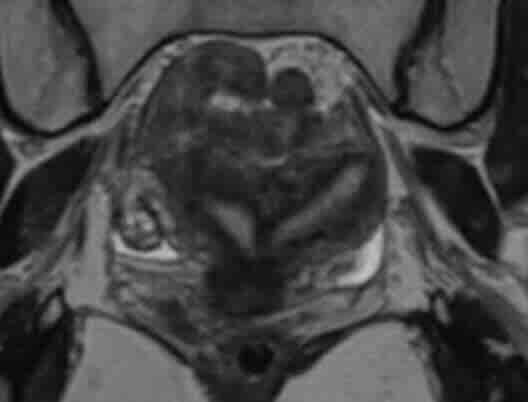

Rahim içi perde (septum) HSG’de belli olur mu?

HSG’de rahim iç boşluk şekli değiştiği için perde şüphesi görülebilir. Ancak tanıyı netleştirmek için 3D ultrason, MRI veya histeroskopi gerekebilir. Tedavi planı bu doğrulamaya göre yapılır. -